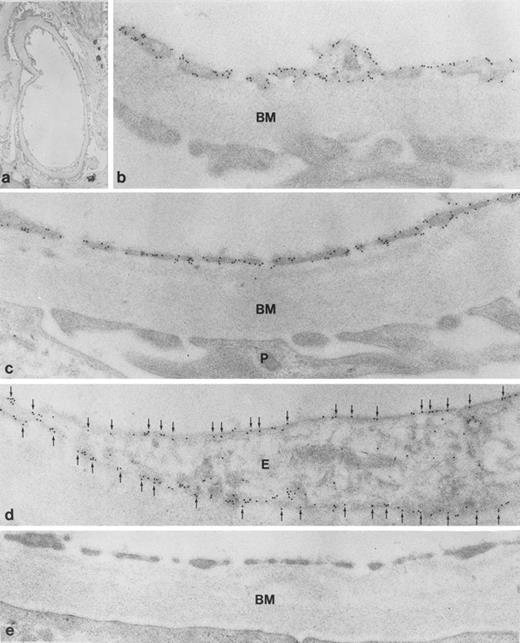

To define the subcellular localization of gp-Fy, ultrathin sections were analyzed under the electron microscope. Capillary endothelial cells exhibited abundant labeling of apical and basal plasma membrane domains with labeling extending into fenestrations (Fig 4). This labeling pattern was evident in glomerular capillaries (Fig 4b) and peritubular capillaries in the cortex (Fig 5c). The principal epithelial cells of collecting ducts exhibited extensive labeling (Fig 5b) and strong labeling of caveoli was also observed (Fig 6a and b). Podocytes were not labeled (Fig 4c). Immunolabeling controls were negative (Figs 4e and and 5d and e).

Immunoelectron microscopic localization of gp-Fy in the inner medulla of kidney vascular structures. Extensive labeling is seen of plasma membranes and multiple caveoli (arrows). BM, basement membrane; N, nucleus. (Original magnification × 35,000 [a] and × 24,000 [b].)

Endothelial cells are known for having caveolae or noncoated plasmalemmal vesicles, glycolipid microdomains rich in cholesterol, glycosyl phosphatidylinositol (GPI)-anchored protein and caveolin.35 Duffy protein, as a transmembrane protein, is present also in caveolae (Fig 6) and may participate in receptor-mediated endocytosis.36 Recently, the endocytosis of radiolabeled chemokines in K562, transfected with gp-Fy cDNA was shown.19 Possibly, gp-Fy, as a receptor for small molecules (polypetide or amino acids), uses this membrane domain for endocytosis.